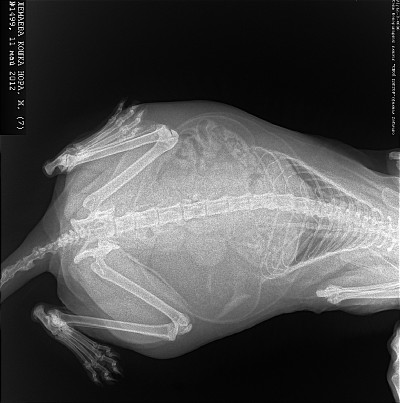

Дистрофия у кошек